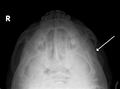

Fracture of the zygomatic arch as seen on plain Xray- Zygomatic arch.Base of skull.